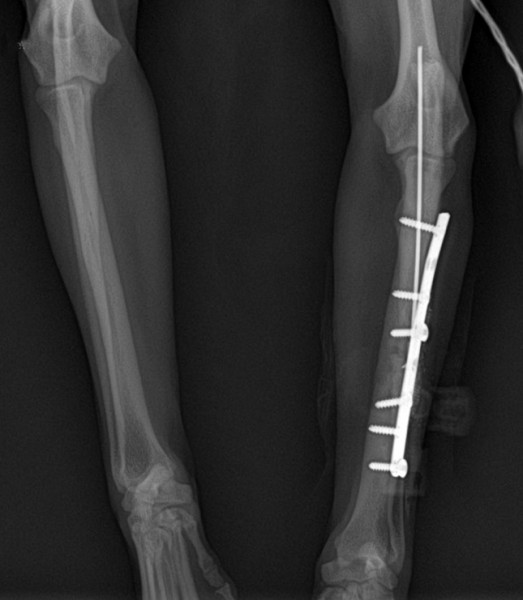

• les atteintes de la structure, nécessitant un abord médical classique ; un os fracturé, un ligament arraché, un organe au tissu dégradé, sclérosé, une tumeur,….

• état post-traumatique : après un accident ou une opération, après un choc psychologique ou émotionnel important.